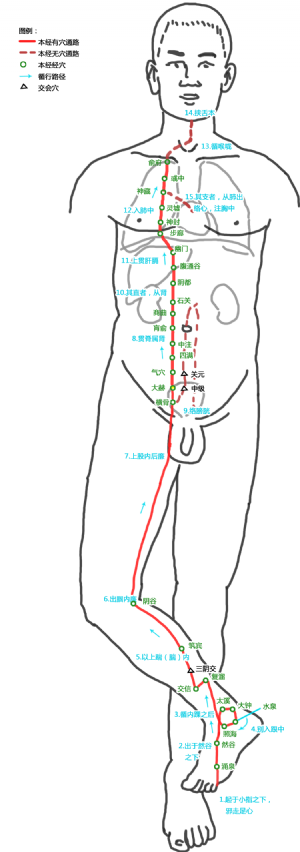

大赫爲經穴名(Dàhè KI12)[2]出《鍼灸甲乙經》。別名陰維、陰關[3]。屬足少陰腎經[3]。大赫是衝脈、足少陰腎經的交會穴[3][3]。大爲小之對,赫即顯赫,穴之所在相當於下焦元氣顯赫盛大之處,故名大赫[3]。大赫穴主治肝腎,前陰部等疾患:如少腹急痛,虛勞失精,陰上縮,莖中痛,女子赤白帶下,陰挺,遺精,帶下,月經不調,痛經,泄瀉,少腹痛,陽痿,疝氣,現代又多用大赫穴治療精液缺乏症,精索神經痛,性機能障礙,慢性陰道炎,膀胱炎,早泄,睾丸炎,盆腔炎等。

3.6 陰維穴的定位

標準定位:大赫穴在下腹部,當臍中下4寸,前正中線旁開0.5寸[6]。

大赫穴位於下腹部,臍中下4寸,前正中線旁開0.5寸[6]。仰臥取穴[6]。

大赫穴位於腹正中線臍下4寸,旁開0.5寸處(《銅人腧穴鍼灸圖經》)[6]。

另說在臍下3.5寸,旁開0.5寸(《鍼灸甲乙經》);臍下4寸,旁開1寸(《鍼灸大成》);臍下4寸,旁開1.5寸(《鍼灸資生經》)[6]。

大赫穴在下腹的位置

大赫穴在下腹的位置

3.7 陰維穴的取法

大赫穴位於下腹部,臍中下4寸,前正中線旁開0.5寸[6]。仰臥取穴[6]。

仰臥位,當恥骨聯合上緣中點上1寸,前正中線旁開0.5寸處取穴[7]。